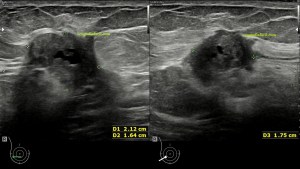

Era un nódulo hiperecogénico en el contexto de la tiroiditis en el estudio de una ecografía tiroidea.

Te enseño las imágenes, típicas de una exploración tiroidea de protocolo con semiología de tiroiditis.

De la imagen 1 a 7 el protocolo habitual, el estudio particular del nódulo con medidas y aplicación del doppler demuestra el aspecto típico del Caballero Blanco.

De la 8 a la 11 estudio con Doppler.

La imagen 12 y 13 están adquiridas con una sonda de 18 Mhz.

En la 14 un ganglio reactivo con medidas respetadas.

El el 15 tienes un vídeo de un corte axial de El Caballero Blanco.

Resumen de las imágenes que has visto en el caso de hoy:

1. Hipoecogenicidad del parénquima

2. Heteroecogenicidad

3. Múltiples nódulos hipoecoicos muy pequeños

4. Doppler Color y Doppler Power aumentado de tamaño en el nódulo

Este es el aspecto ecográfico descrito anteriormente de la patología que habitualmente puede albergar el nódulo del que trata hoy el post y que no es otra que la de la Tiroiditis de Hashimoto.

El Caballero blanco, recibe el nombre debido a su semiología hiperecogénica, homogénea y solitaria circunscrito en la patología referida con anterioridad, puede aparecer en esta patología de forma benigna o degenerar en otro tipo de patología a formas malignas como el linfoma tiroideo.